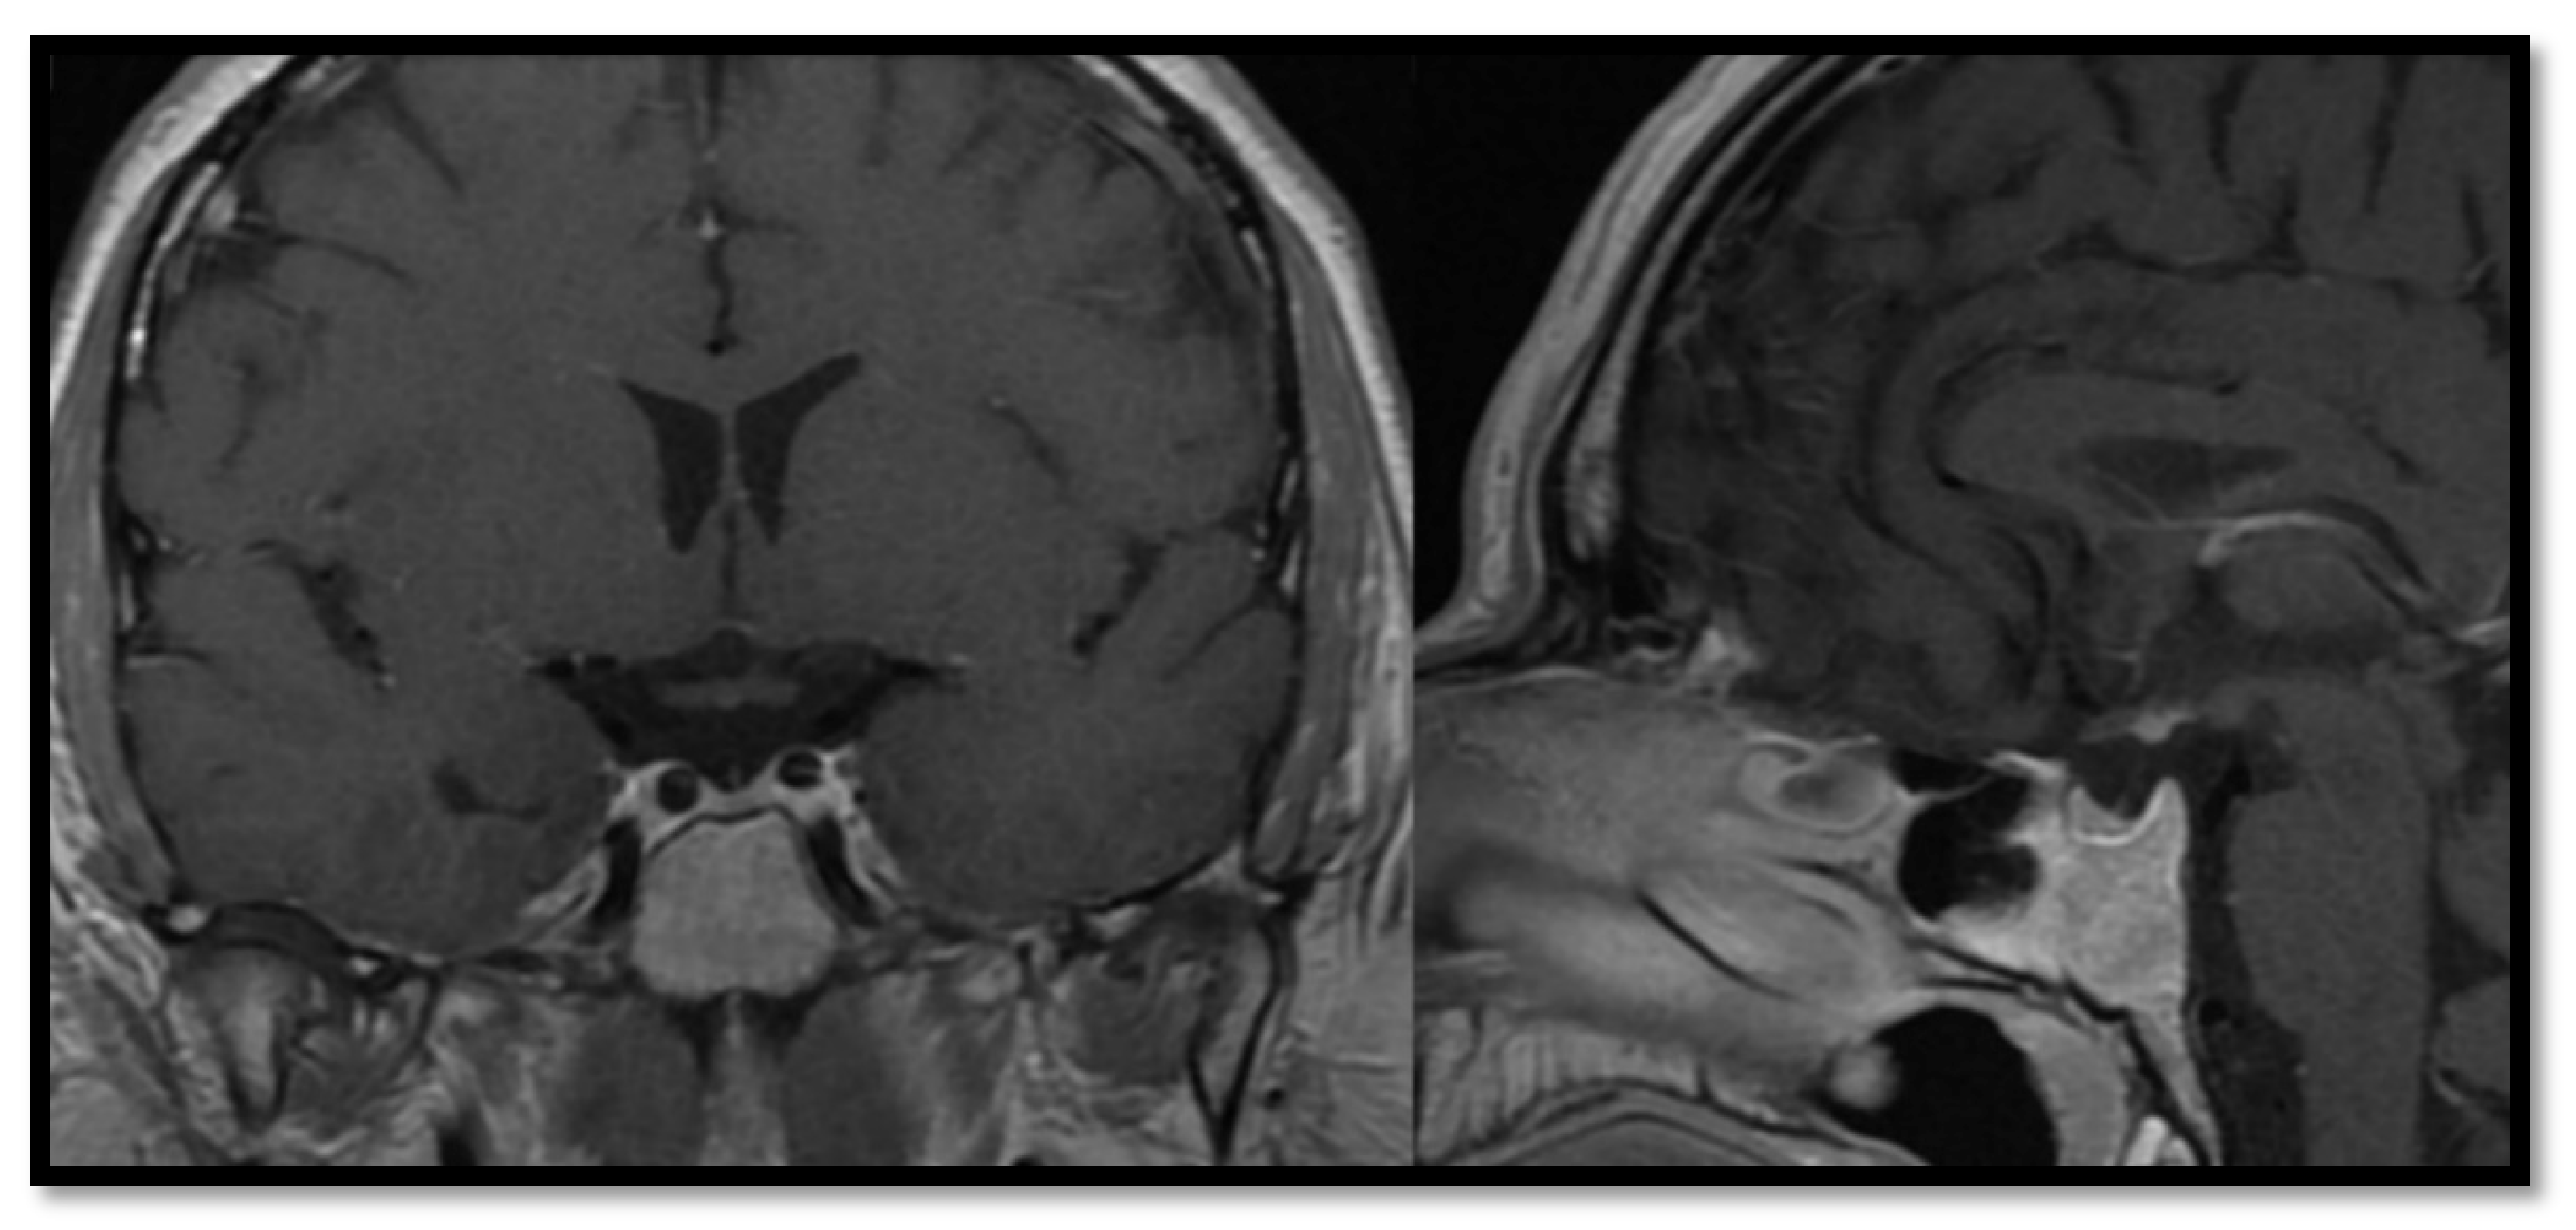

3.2. Inflammatory Processes

3.4. Imaging